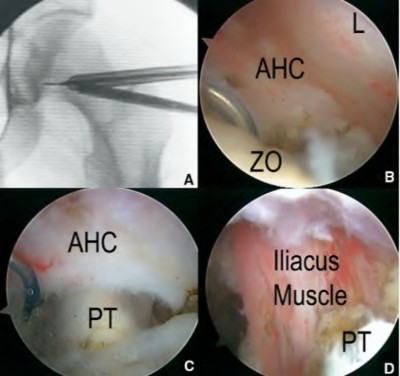

Figures A and B are pre-operative and intra-operative radiographs of a 67-year-old male that has undergone a left total hip arthroplasty under general anesthesia. The patient had no motor deficits preoperatively. During the operation, the trial acetabular and femoral components were positioned and reduced with no complication. Intraoperative leg lengths were equal. Before implanting the real components, the surgeon and anaesthesiologist performed a wake up test, which revealed that the patient was unable to dorsiflex the left foot. What would be the most appropriate next step in the management of this patient?

This patient has undergone a left THA with significant leg lengthening. The biggest concern is stretch to the sciatic nerve. The most appropriate step at this stage would be to perform a subtrochanteric osteotomy to decrease leg length and sciatic nerve stretch.

Patients with DDH that have undergone a large limb-lengthening procedure are at a greater risk due to the significant stretch of the sciatic nerve. Intraoperative procedures that have been shown to prevent this outcome include good pre-operative planning, limb lengthening